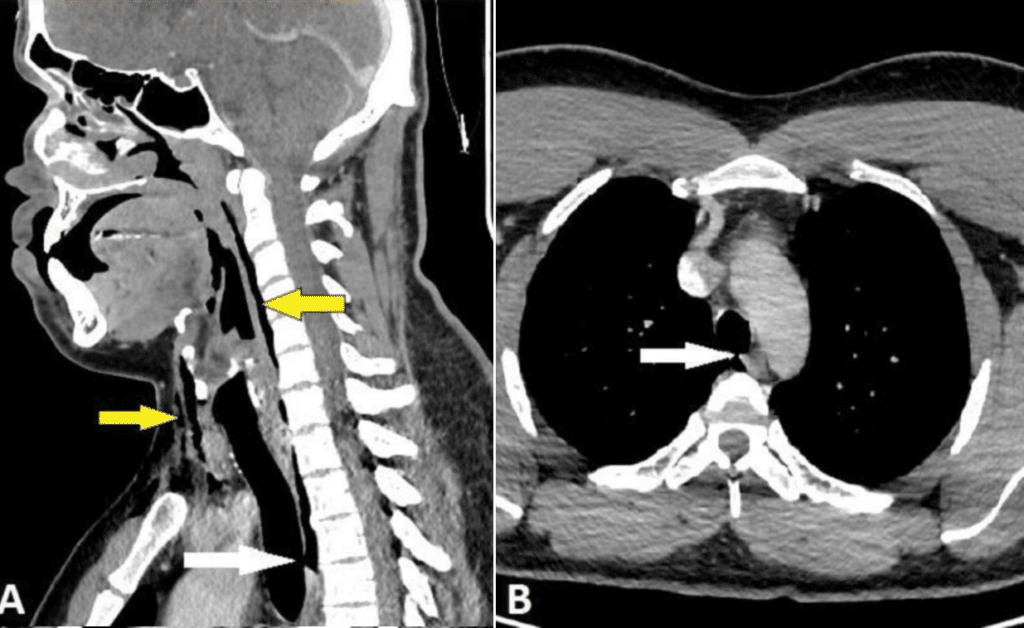

“All’esame obiettivo, il collo era gonfio da entrambi i lati, mostrava un lieve crepitio alla palpazione e un ridotto range di movimento. La radiografia laterale dei tessuti molli del collo ha rivelato un enfisema a livello del collo. Successivamente, la TAC del collo e del torace con mezzo di contrasto ha evidenziato una lesione tracheale di 2 mm x 2 mm x 5 mm a livello tra la terza e la quarta vertebra toracica, con pneumomediastino ed enfisema del collo”.